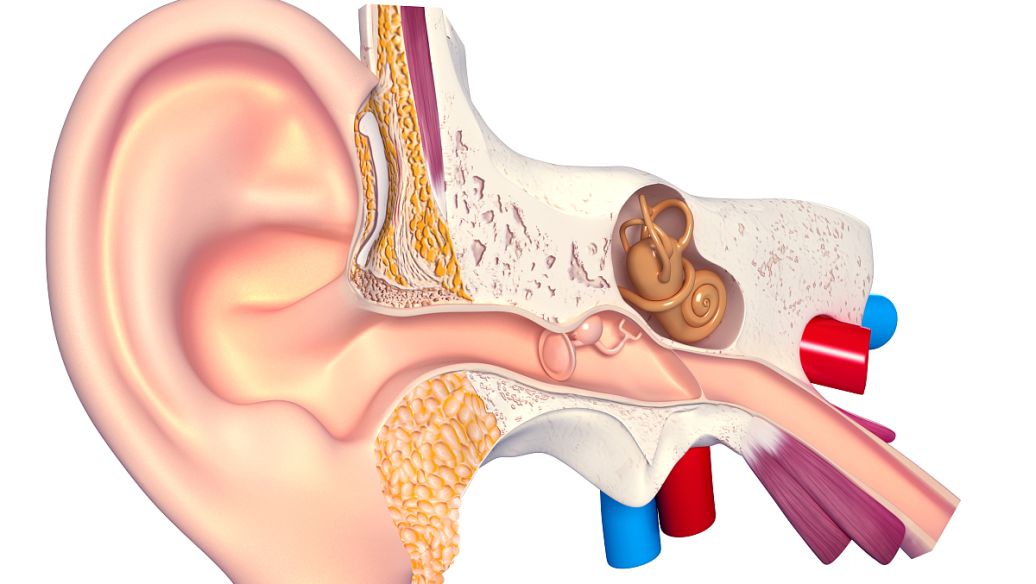

对于人体中的核磁共振成像,通常以氢核为目标,因为其中水和脂肪中有很多,然后图像的亮度基本上可以告诉我们脂肪和水的数量。人们也可以瞄准其它原子核并进行测量,这就导致了不同核磁共振图像的工作方式不同。核磁共振成像非常适合于检查软组织,而对于骨折一般则使用X射线成像。